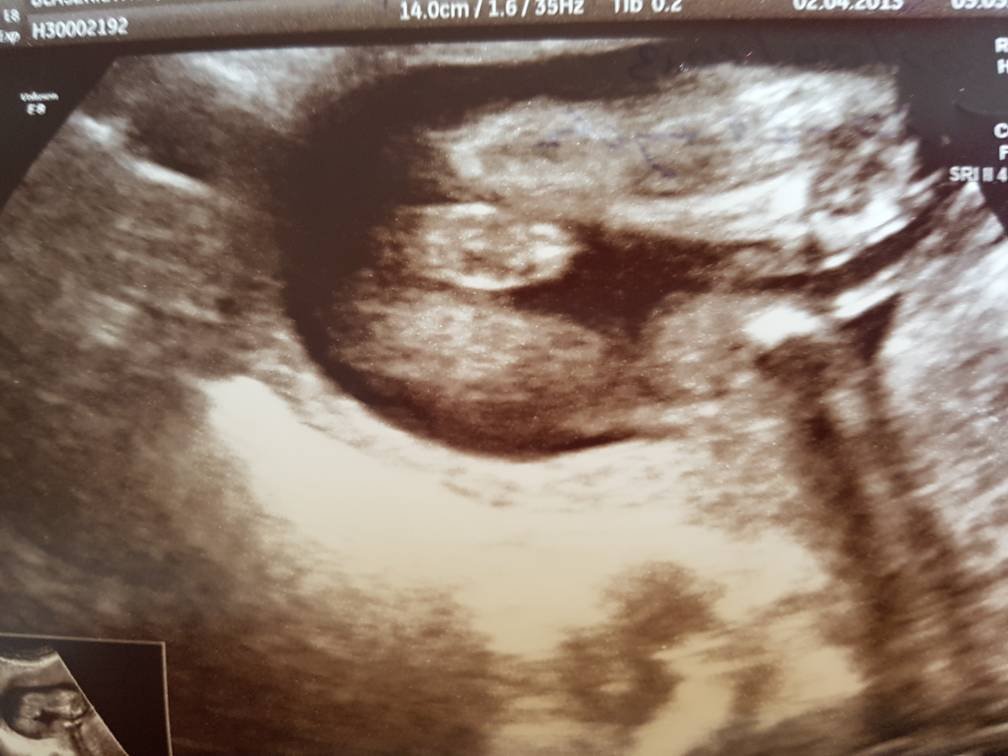

Cześć, mogę dołączyć się do wróżenia? Już mnie tak roznosi z niecierpliwości, dzidzia 7 cm, zdjęcie 14 tydzień :) Mi się wydaje, że dziewczynka :)

Załączniki

• img20190106_16433978.png

img20190106_16433978.png

869,2 KB · Wyświetleń: 452

Bardzo dziękuję za wyjaśnienie bo zupełnie nie mialam.o tym pojęcia najważniejsze jest zdrowie dziecka. Ale cały czas podświadomie czuję dziewczynkę. Gdy lekarz w sumie bez przekonania bo dziecko za bardzo się wierciło powiedział chłopak nie mogłam uwierzyć. Później dwa razy było że dziewczynka i jestem zupełnie zagubiona. A na tym moim USG ten siusiak wydaje się mi zwyczajnie za duży. Przy pierwszym.Synku